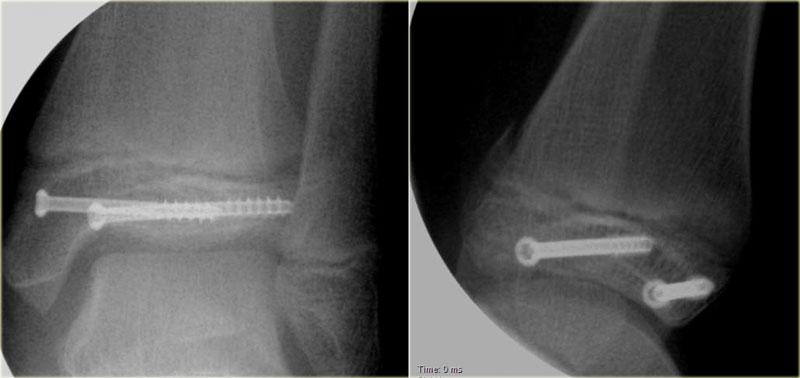

Trong phẫu thuật, cổ chân được xác định là không vững và vít cố định khớp chày mác đã được đặt vào.

Có chỉ định cố định gãy mắt cá sau vì mảnh gãy chiếm hơn 25% diện khớp của đầu dưới xương chày.